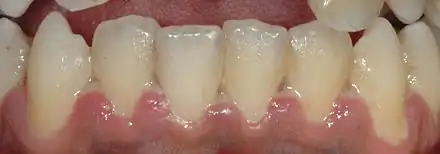

Gingivite ulcéronécrotique (GUN) au niveau des gencives des dents antérieures de la mandibule.

La gingivite ulcéronécrotique (GUN) se caractérise par des lésions nécrotiques au niveau de la gencive marginale, des zones de nécrose recouvertes d'une pseudomembrane blanc jaunâtre de consistance molle faite de leucocytes et de bactéries (la zone ulcéreuse est sous-jacente). L'ulcère nécrotique commence au sommet de la papille et la sépare en un versant vestibulaire et un lingual. Il y a une gingivorragie spontanée, une halitose fréquente et parfois des adénopathies.

Au début, une seule papille est touchée mais l'atteinte peut s'étendre aux autres papilles avec un lien nécrotique. La nécrose peut s'étendre sur toutes les faces vestibulaires, plus rarement sur les faces linguales ou palatines.